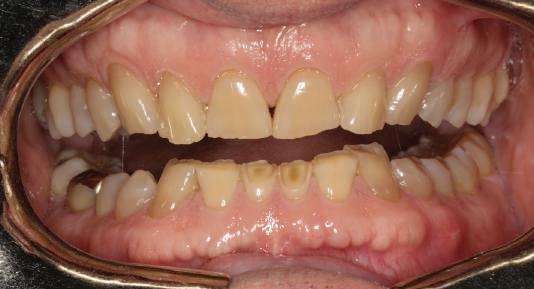

Reprepararea intraorală a bonturilor Acest pacient prezenta dentiţia maxilară compromisă, refuzând proteza mobilizabilă. Prin abordarea în etape, se menţin o parte din bonturile dentare naturale; s-a observat recesie în momentul amprentării pentru cel de-al doilea grup de implanturi.

Fig. 1 prezintă pacientul după inserarea primului set de bonturi implantare individualizate; dinţii naturali adiacenţi

sunt încă prezenţi pentru a susţine puntea provizorie.

Şapte luni mai târziu (fig. 2), acele bonturi individualizate din prima etapă au manifestat semne de recesie de 1-3mm. Atitudine: S-a decis reprepararea intraorală a tuturor bonturilor (fig. 3), astfel încât toate marginile bonturilor să fie la nivelul sau sub marginea gingivală (de notat că 1.1. şi 2.1. au fost submersaţi ulterior pentru a avea sprijin implantar deplin).

Deşi reprepararea a îmbunătăţit marcat estetica finală, a necesitat aplicarea şnurului de retracţie, amprente noi şi turnări noi.

Un caz separat dar similar ilustrează în figurile 4 și 5 reprepararea intraorală a bontului.

Cazul (1): Reprepararea intraorală a bonturilor Figurile

1. Aspect după inserarea primului set de bonturi implantare individualizate.

2. După 7 luni, bonturile individualizate din prima etapă au prezentat recesie de 1-3mm.

3. Bonturile repreparate intraoral.